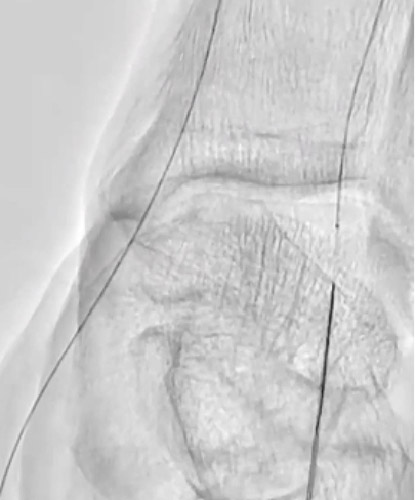

DAは閉塞していたが内腔はあるので穿刺を検討したが、難しいと判断しPTAを穿刺した。PTA経由でATAにレトログレードアプローチを行いDAからシースを挿入するため、1gワイヤーを進めたがATA(Anterior Tibial Artery)方向へワイヤリング出来ないため、Zizai™をPOP方向へ進め造影した(図3)。ATA入口部は狭窄しており、更に末梢は閉塞していることを確認した。ATA入口部へワイヤー通過に成功し急峻な角度ではあったがZizai™を追従させ(図4)、ATAは閉塞血管でありワイヤールートはSubでも良いと判断しワイヤーナックルにて末梢まで進めた。DAを18G針で穿刺をしワイヤーランデブーに成功した(図5)。その後、DAに4Frシースを挿入し、2.5㎜径バルーンでATAを拡張したあと、PTAのワイヤーとZizai™を抜去後にアプローチサイトの止血を行い、ATAの4Frシースからガイディングシースへ入れ替えを行った。

ガイディングシースから造影を行い、SFAの石灰化を伴う短いCTO病変を確認した(図6)。6gワイヤーで石灰化を縫うようにdrillngをし、ワイヤー通過に成功した。血管狭窄部貫通用カテーテルでCTO部分を通過させた後に、4㎜径のバルーンで拡張を行った。OFDIで血管内を観察すると突出する石灰化及び、Distal部分は解離を認めた(図7)がルーメンは確保出来ていた。石灰化部分に4㎜径のcutting balloonで拡張を追加しルーメンは確保(図8)できたが、圧較差は改善しなかったため更にProximal側の病変(図9)に4㎜径のcutting balloonで拡張しDES 7㎜×150㎜を留置した。Distal側はDCB 4㎜×200㎜を施行した。最終造影では病変部は拡張出来ており、圧較差がなくなったことを確認し終了した。(図10)今回の様にPTAは開通しているがATAは閉塞している様な症例でTAIを行う際、PTAからシースを挿入するとPTAも閉塞してしまいCLTIを招いてしまう恐れがある。今回の様な場合は閉塞しているATA経由のTAIを行うことが重要と考える。